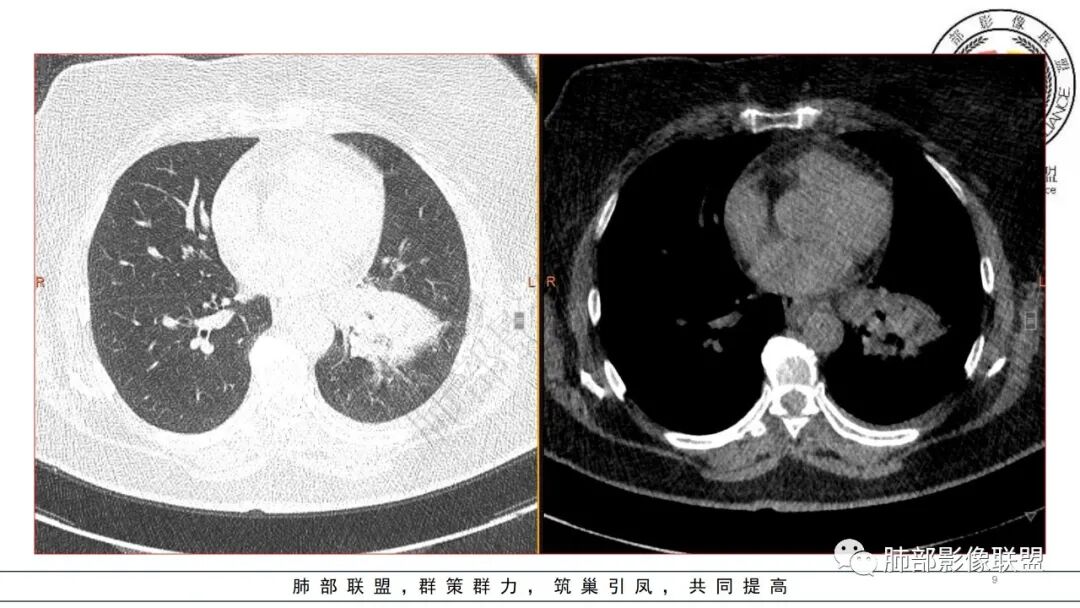

2.左肺下叶大范围实性密度影,散乱,边界不清,可见液化空洞,病变肺体积轻度增大。支气管相关(相应支气管闭塞)。

3.五天后及十三天后病灶变化明显,实性密度影吸收缩小,边界趋于清楚,显示多空腔。

5.扫描范围内未见肝脏密度异常影。

1.局限于单肺叶的大范围实性密度影,边界不清,看不出外壁的液化空洞,多符合化脓性感染。

4.肺炎克雷伯杆菌肺炎病灶也易形成脓腔。本例患者未出现典型金葡感染影像学特征,患者临床表现相对“逍遥”缓慢,结合实验室检查,更符合肺炎克雷伯杆菌肺炎。

肺克的鉴别点,肺克多来自血播,所以肺克的典型影像是标准的SPE,SPE的过程中有动态表现,实变-反晕-空洞液化,是一个发展过程。

金葡应该也是血源性来源,因此也存在鉴别,区别在肝脏,肺克的血播是肝脏来源,金葡的血播可以各种来源,但是一般不会是肝脏来源,具体来说,金葡的SPE观察不那么典型,金葡可以形成更大的实变,肺克少一些,金葡的特征应该还是气囊,壁的张力更高,更薄,SPE似乎不明显,临床上皮肤软组织脓肿的有无,这个特征肺克应该不具有,但肺克一般有肝脓肿,没有的少见。